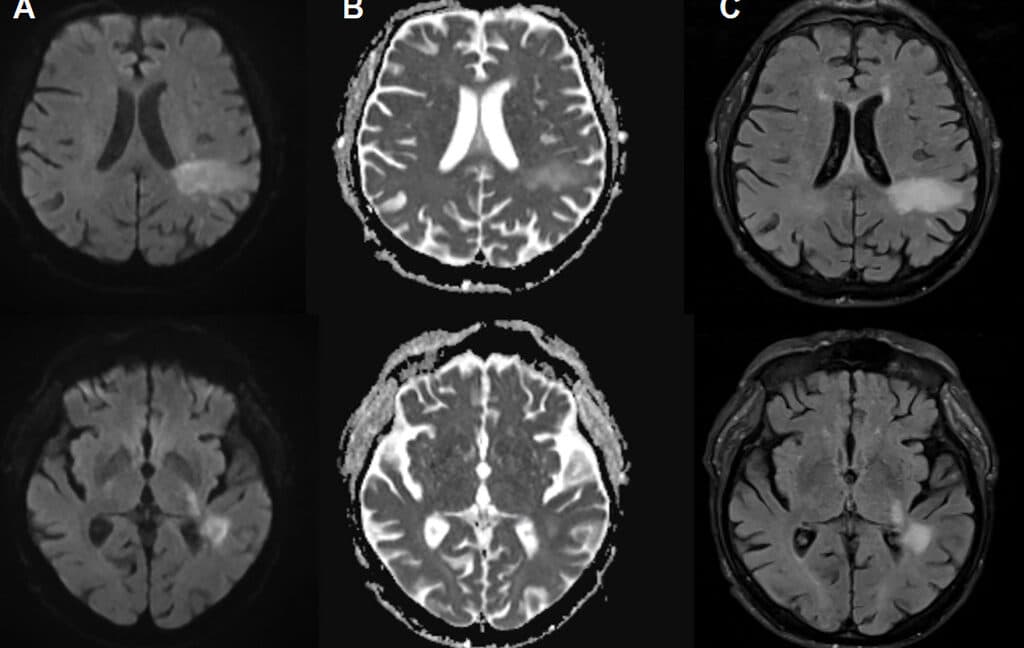

A recent study reveals that a fatal brain infection, previously attributed to severe immune suppression, may actually be caused by a brain-eating virus that many are unknowingly infected with. This discovery challenges existing beliefs about the origins of the infection and raises concerns about its prevalence. The implications of this finding could lead to new approaches in diagnosis and treatment.

Historically, fatal brain infections have been linked to compromised immune systems, but emerging evidence suggests that a previously unidentified virus may be a common factor. This change in perspective could reshape how healthcare providers approach diagnosis and treatment of similar conditions.